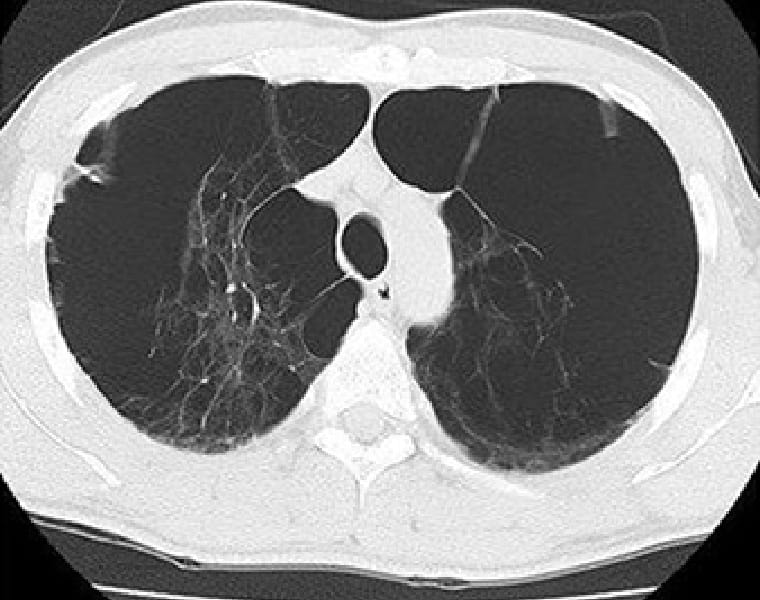

血液検査と尿検査に加えて、医師は腹部/腎臓の CT スキャンを指示する場合もあります。この検査では、X 線画像を使用して腎臓と腹部の内部を観察します。これは、症状の他の潜在的な原因を除外するのに役立ちます。